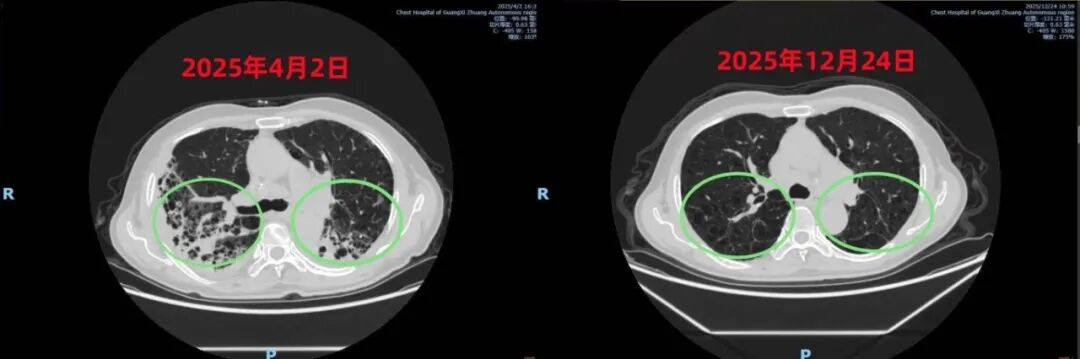

胸部CT前后对比

从依赖呼吸机到成功脱机,从各项指标异常到正常,患者的每一点点好转,都凝聚着结核科一病区医护人员的坚持与合作。在医护共同努力下,患者咳嗽、咳痰、气促的症状明显缓解,各项指标逐渐恢复正常,最终顺利康复出院。在后期的随访中,医护人员得知其还重返了工作岗位,恢复了正常的生活能力。近日,王先生完成了9个月的肺结核治疗方案,经复查,已治愈。